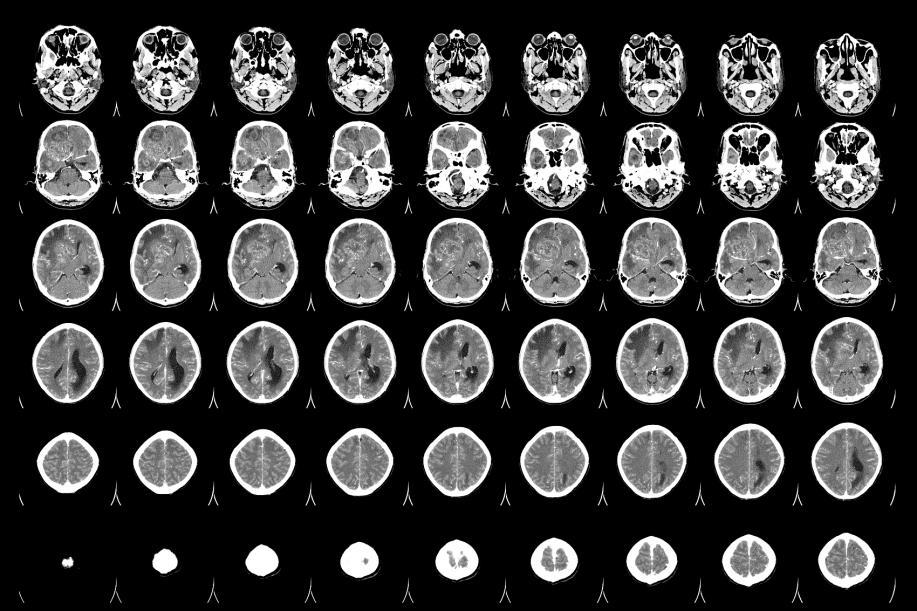

胶质瘤放射治疗是一种常见的治疗方法

胶质瘤放射治疗技术,昆明治疗晚期胶质瘤医院推荐-昆明医科肿瘤医院胶质瘤是一种严重的脑部恶性肿瘤,它起源于神经胶质细胞,通常发生在大脑的深处。胶质瘤的治疗通常涉及手术、放疗和化疗。在这篇文章中,我们将重点介绍胶质瘤放射治疗的相关知识。放射治疗是一种常见的治疗胶质...

胶质瘤放射治疗的适应症有哪些

胶质瘤的早期症状,昆明治疗胶质瘤医院哪家好-昆明医科肿瘤医院胶质瘤是一种常见的脑部肿瘤,通常需要采用综合治疗来控制其生长和扩散。放射治疗作为胶质瘤治疗中的重要手段,可以减少肿瘤的大小和数量,从而改善患者的生活质量和延长生存期。本文将介绍胶质瘤放射治疗的基本情况...

胶质瘤放射治疗的基本原理、治疗方法和注意事项

胶质瘤放射治疗效果,昆明晚期胶质瘤治疗医院推荐-昆明医科肿瘤医院胶质瘤是一种常见的恶性脑肿瘤,常常难以完全切除。放射治疗是治疗胶质瘤的重要手段之一,可以通过辐射杀死肿瘤细胞、抑制肿瘤生长和复发,提高患者的生存率和生存质量。本文将介绍胶质瘤放射治疗的基本原理、治...

胶质瘤放疗相关知识科普

晚期胶质瘤治疗方案,昆明胶质瘤医院效果好的医院-昆明医科肿瘤医院胶质瘤是一种恶性肿瘤,起源于脑中的胶质细胞,是脑肿瘤中最常见的类型。胶质瘤通常会通过手术切除、放疗和化疗等治疗方法进行治疗。其中,放疗治疗在胶质瘤治疗中扮演着重要的角色,本篇文章将会详细介绍胶质瘤...

胶质瘤的治疗效果到底好不好

胶质瘤治疗效果如何,昆明胶质瘤医院哪家还不错-昆明医科肿瘤医院放射治疗是胶质瘤治疗的常用方法之一。下面我们来了解一下放射治疗在胶质瘤治疗中的作用。放射治疗是利用高能射线或粒子对癌细胞进行杀伤的一种治疗方法。放射治疗可以直接杀死癌细胞或阻止它们继续生长和扩散。对...

胶质瘤的治疗方式有哪些

胶质瘤的治疗方式,昆明胶质瘤医院排名推荐-昆明医科肿瘤医院胶质瘤是一种难以治愈的恶性肿瘤,因其高度侵袭性和复发性而难以治疗。目前,治疗胶质瘤的方法主要包括手术切除、放射治疗和化学治疗等综合治疗手段。本文将介绍各种治疗方法的优缺点以及选择治疗方案的考虑因素。手术...

胶质瘤的预后取决于多种因素

胶质瘤的预后效果,昆明胶质瘤医院哪家好-昆明医科肿瘤医院脑胶质瘤是由于大脑和脊髓胶质细胞癌变所产生的、最常见的原发性颅脑肿瘤。年发病率约为3-8人/10万人口。如同其他肿瘤(疾病)一样,胶质瘤也是由于先天的遗传高危因素和环境的致癌因素相互作用所导致的。一些已知...